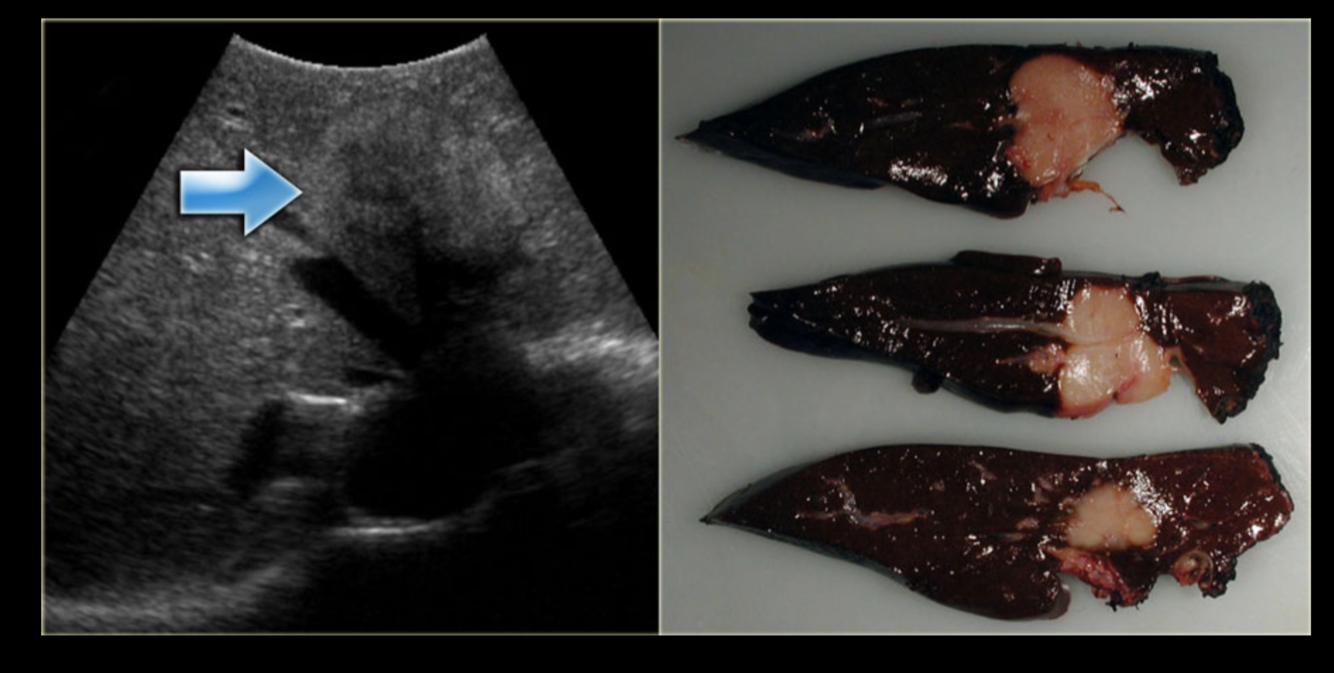

Q

what is this?

what are the associations?

What is the pathology?

A

Splenic Haemangioma

• Case Discussion

The case was operated laparoscopically and the surgeon extended the incision to deliver the enlarged spleen. It is proved to be a bleeding splenic haemangioma. Splenic haemangioma is regarded as the commonest benign splenic tumour and the second commonest focal lesion involving the spleen.